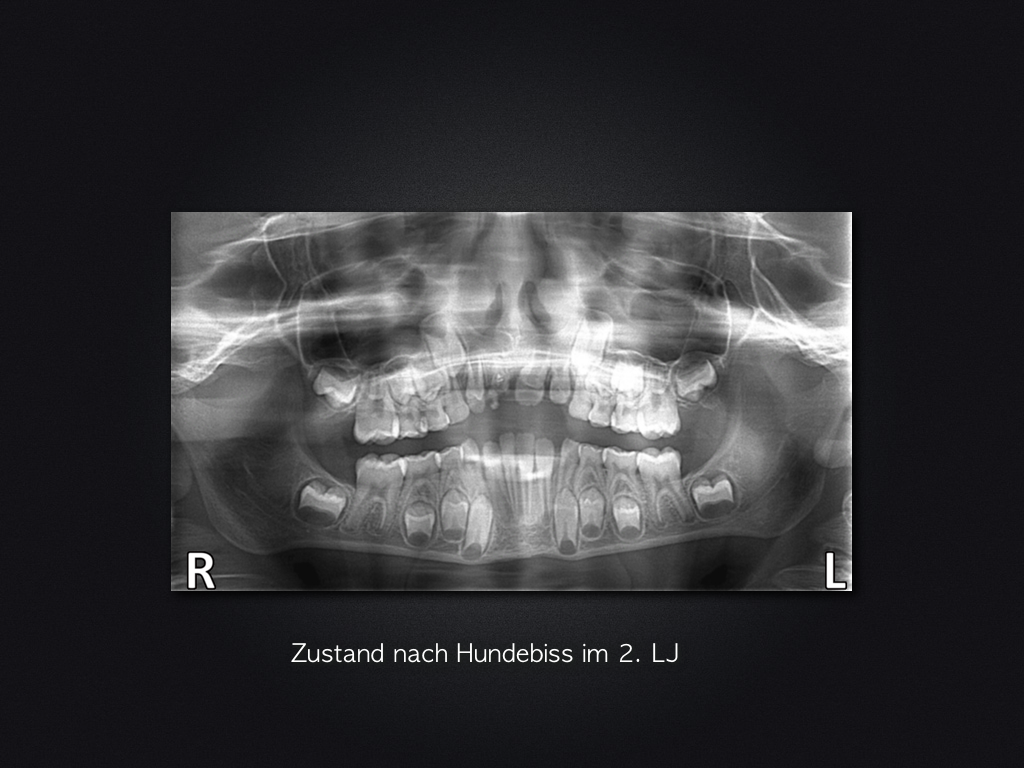

11D.001 Veröffentlicht 13. Juni 2017 am 1024 × 768 in Frontzahntrauma nach Hundebiss – 4 Jahres-Recall